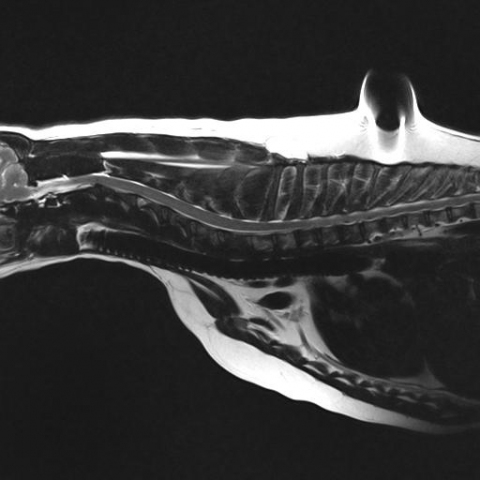

The MRI revealed Dixie to have a compression of her spinal cord, caused by the material that makes up the cushion between the bones of the spinal column spilling out and compressing the cord. The compression was in a precarious position high up in the spinal column and to address the compression would not be an easy feat.

As with any surgery the owner and vet must come to a conclusion of what is best for the patient. Dixie was in a significant amount of pain, which despite best efforts, was proving very difficult to manage with pain killers. In addition any additional leakage of disc material could leave Dixie permanently paralyzed. After a long discussion with Dixie’s owners we decided to proceed with surgery to try and remove the compression from around Dixie’s spinal cord. An intricate C2-C3 hemilaminectomy was carried out to create a window in the bone surround the spinal cord and gently tease out the offending material which was compressing the cord.  During the surgery the atmosphere in theatre was tense as there are major blood vessels which traverse this area of the spinal cord, one wrong move could cause major hemorrhage which could prove fatal!